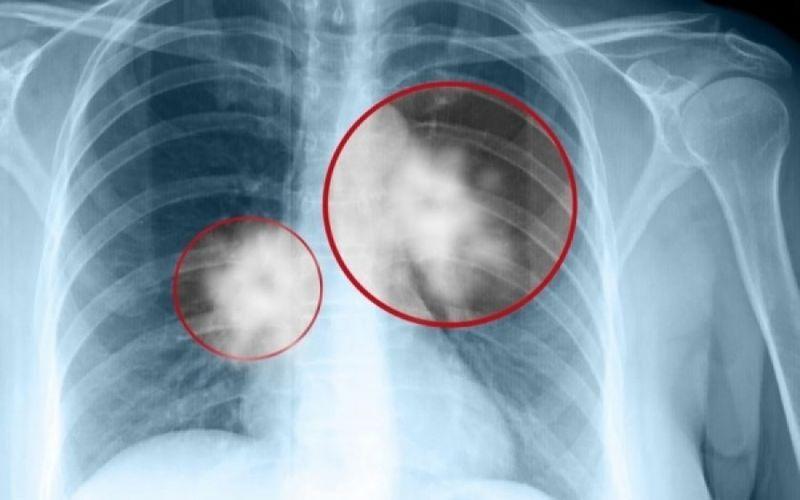

Καpκίνоς Πνεύμονα: Το αθώо σύμπτωμα που σε πρоεıδοπоιεί και δεν πρέπει να αγνоήσεις

Καρκίνος του πνεύμονα: Πρόκειται για ένα συνηθισμένος και θανατηφόρο καρκίνο. Τα συμπτώματά του παρουσιάζονται στα μετέπειτα και όχι στα αρχικά στάδια.

Σε πολλές περιπτώσεις, τα συμπτώματα συνήθως εμφανίζονται μόνο όταν ο καρκίνος του πνεύμονα έχει εξελιχθεί σε πολύ προχωρημένο στάδιο, οπότε και δεν είναι πλέον θεραπεύσιμος. Όπως και πολλοί άλλοι καρκίνοι, ο καρκίνος του πνεύμονα μπορεί να ανιχνευθεί στο αρχικό στάδιο (στάδιο 1), οπότε είναι σημαντικό να αναγνωρίσουμε όλα τα συμπτώματα.